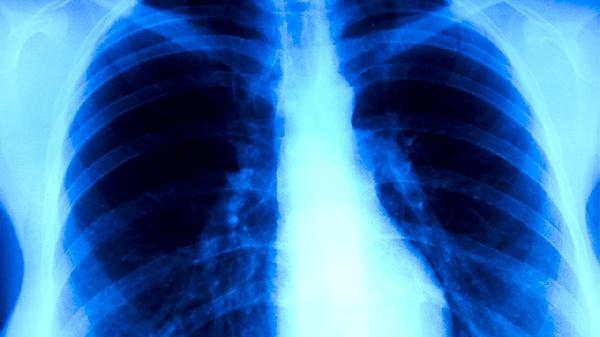

陈旧性肺结核指既往感染结核分枝杆菌后经治疗或自愈遗留的纤维化、钙化病灶。这类患者肺部影像学常显示条索状阴影或钙化点,但痰菌检查阴性且无咳嗽、低热等结核活动症状。对于常规入职体检或健康证办理,若胸片仅提示陈旧性病灶且无传染风险,体检机构通常予以通过。部分特殊职业体检如飞行员、潜水员等对肺功能要求较高,需结合肺通气功能检查结果综合评估。

当陈旧性病灶范围较大导致肺组织广泛纤维化时,可能引起肺活量下降或弥散功能障碍,这类情况可能影响对心肺功能有严格要求的体检项目。若胸片显示病灶边缘模糊伴周围浸润影,或痰涂片检出抗酸杆菌,则提示结核复发需治疗,此时体检不予通过。部分体检机构会要求提供既往结核治疗记录及近期复查报告,以排除活动性结核。